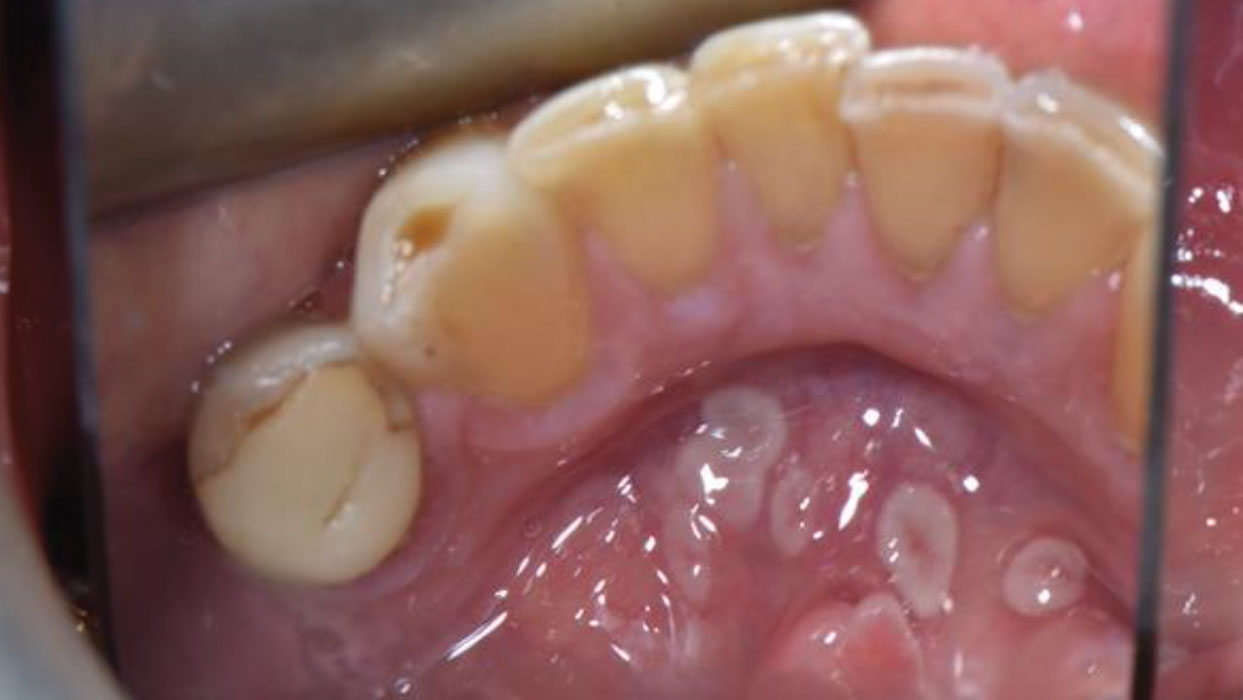

Geographic tongue beyond the dorsum: Clinical and histopathologic diagnosis of ventral tongue and floor-of-mouth lesions

Geographic-tongue-rosenboom alternate text for this image

Geographic tongue (GT), also known as benign migratory glossitis, is a chronic, inflammatory oral condition of unknown etiology.1 It is characterized by erythematous lesions with irregular white borders, and is typically seen on the dorsal and lateral surfaces of the tongue in circinate2 or serpiginous patches.1 The lesions often alternate between periods of exacerbation and remission, and may … Read more